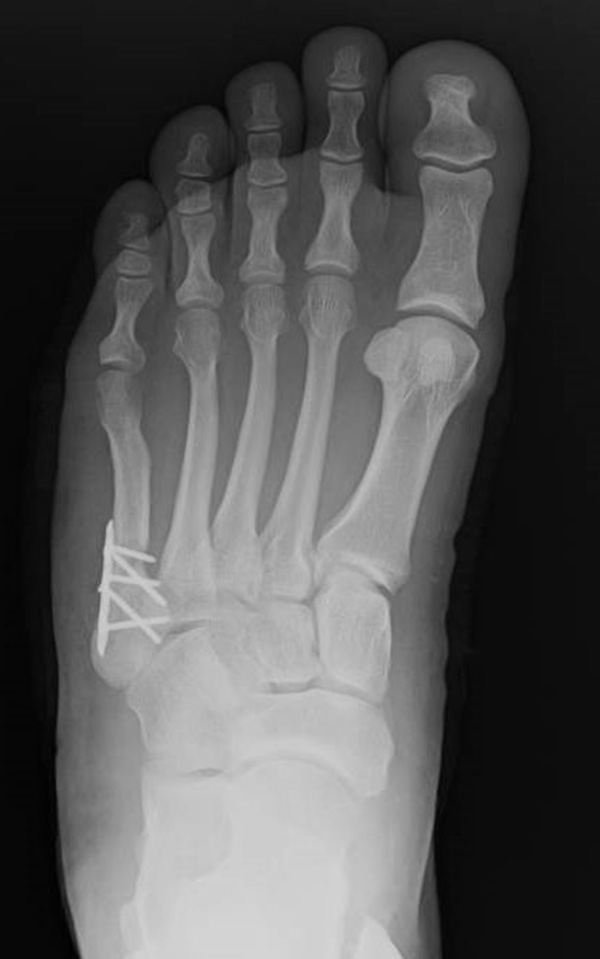

Abb. 12a: Typ III Deformität präoperativ im belasteten dp Röntgenbild.

Abb. 12b: Dorsoplantare Röntgenkontrolle nach medial schließender Osteotomie mit Schraubenosteosynthese.

Abb. 12c: Schrägaufnahme nach medial schließender Osteotomie mit Schraubenosteosynthese.

Abb. 12d: Seitliche Aufnahme nach medial schließender Osteotomie mit Schraubenosteosynthese.